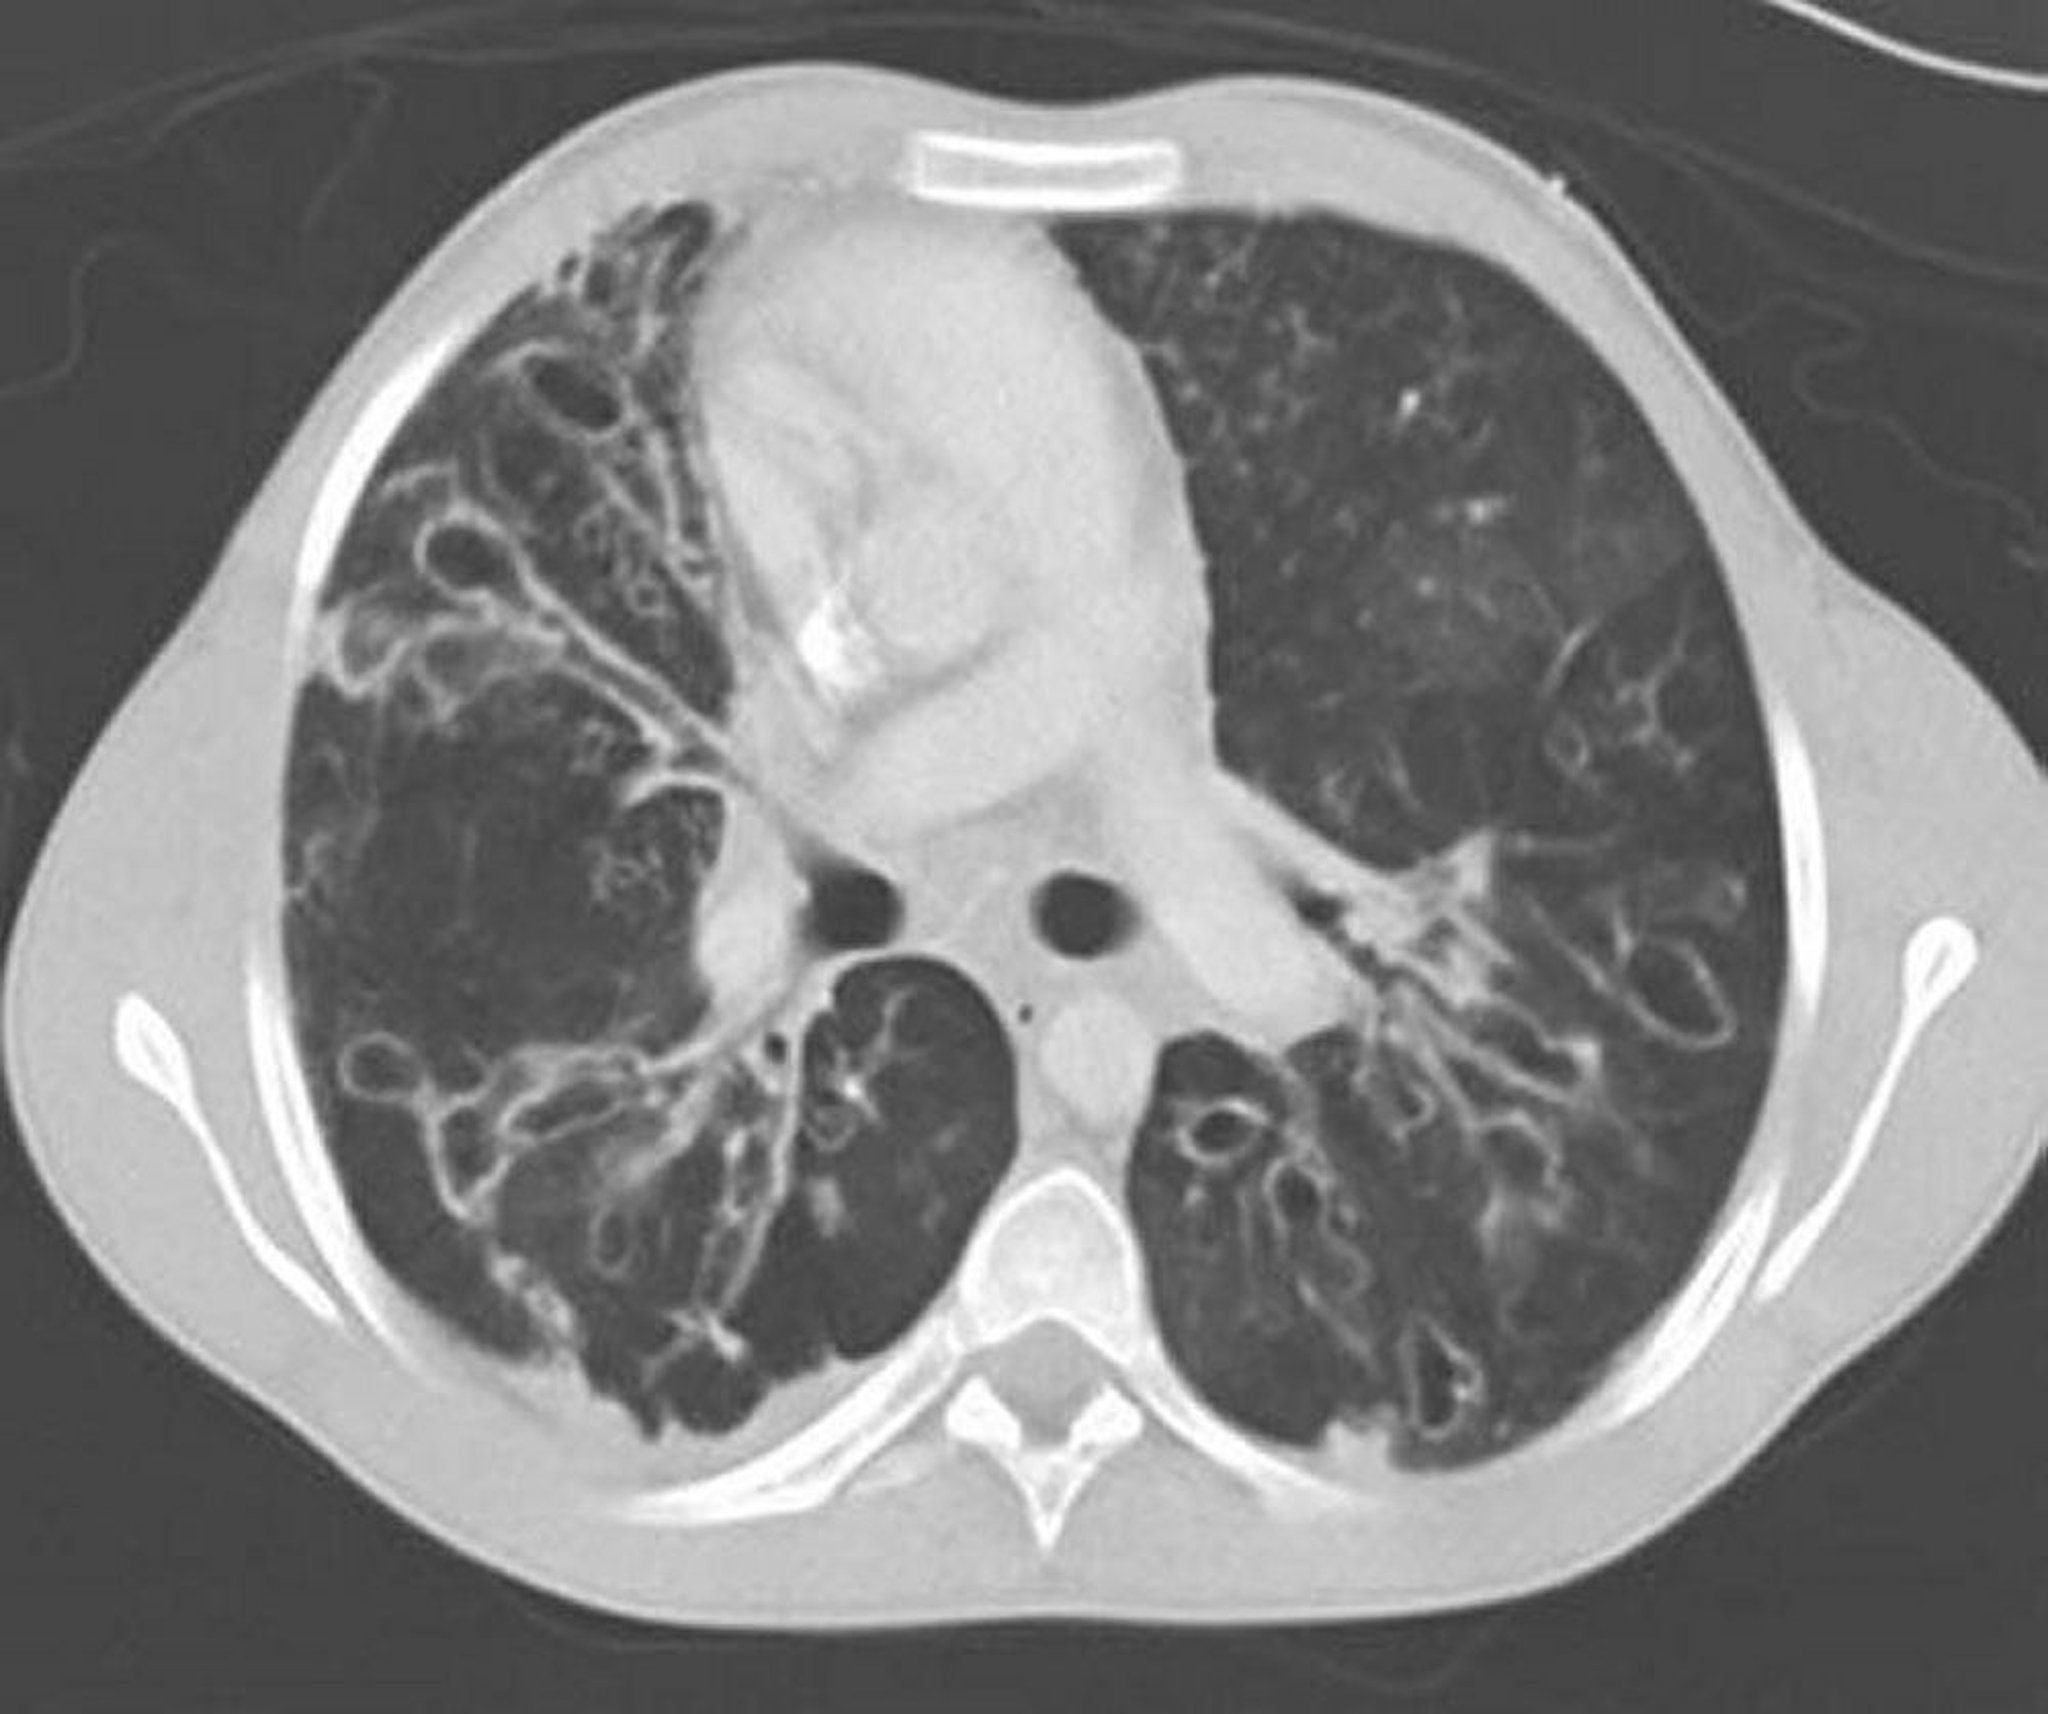

Aspergilosis broncopulmonar alérgica (bronquiectasia)

Una TC de tórax con contraste muestra bronquiectasias graves en las zonas medias del pulmón con vías aéreas muy dilatadas y ectásicas y cambios quísticos. La ectasia de la vía aérea se caracteriza por una relación entre la vía aérea y el vaso adyacente > 1.